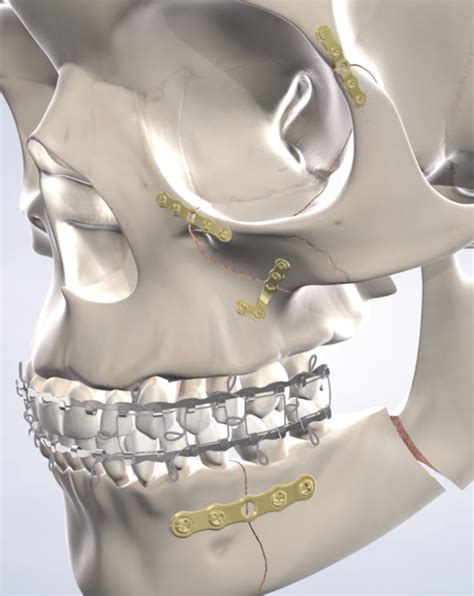

Surgeons typically employ "open reduction and internal fixation" (ORIF) as a standard for treating complex fractures. This involves repositioning the bone segments and securing them with specialized hardware. Below is a summary of the common materials and approaches used in the operating room.

Titanium Micro-plates Provides structural support to bone fractures while healing.

Before any incision is made, the surgical team must obtain a high-definition map of the damage. Modern medical imaging has revolutionized face trauma surgery, allowing surgeons to visualize fractures in three dimensions. Using CT scans and Cone Beam Computed Tomography (CBCT), doctors can identify displaced bone fragments that are not visible to the naked eye. This data is critical for planning the placement of titanium plates, screws, and mesh grafts.

Advancements in 3D printing have also made a significant mark on the field. Surgeons can now print 3D models of a patient's skull to practice the placement of hardware before the actual surgery takes place. This "practice run" reduces the time the patient spends under anesthesia and increases the precision of the final outcome, leading to faster healing and fewer complications.